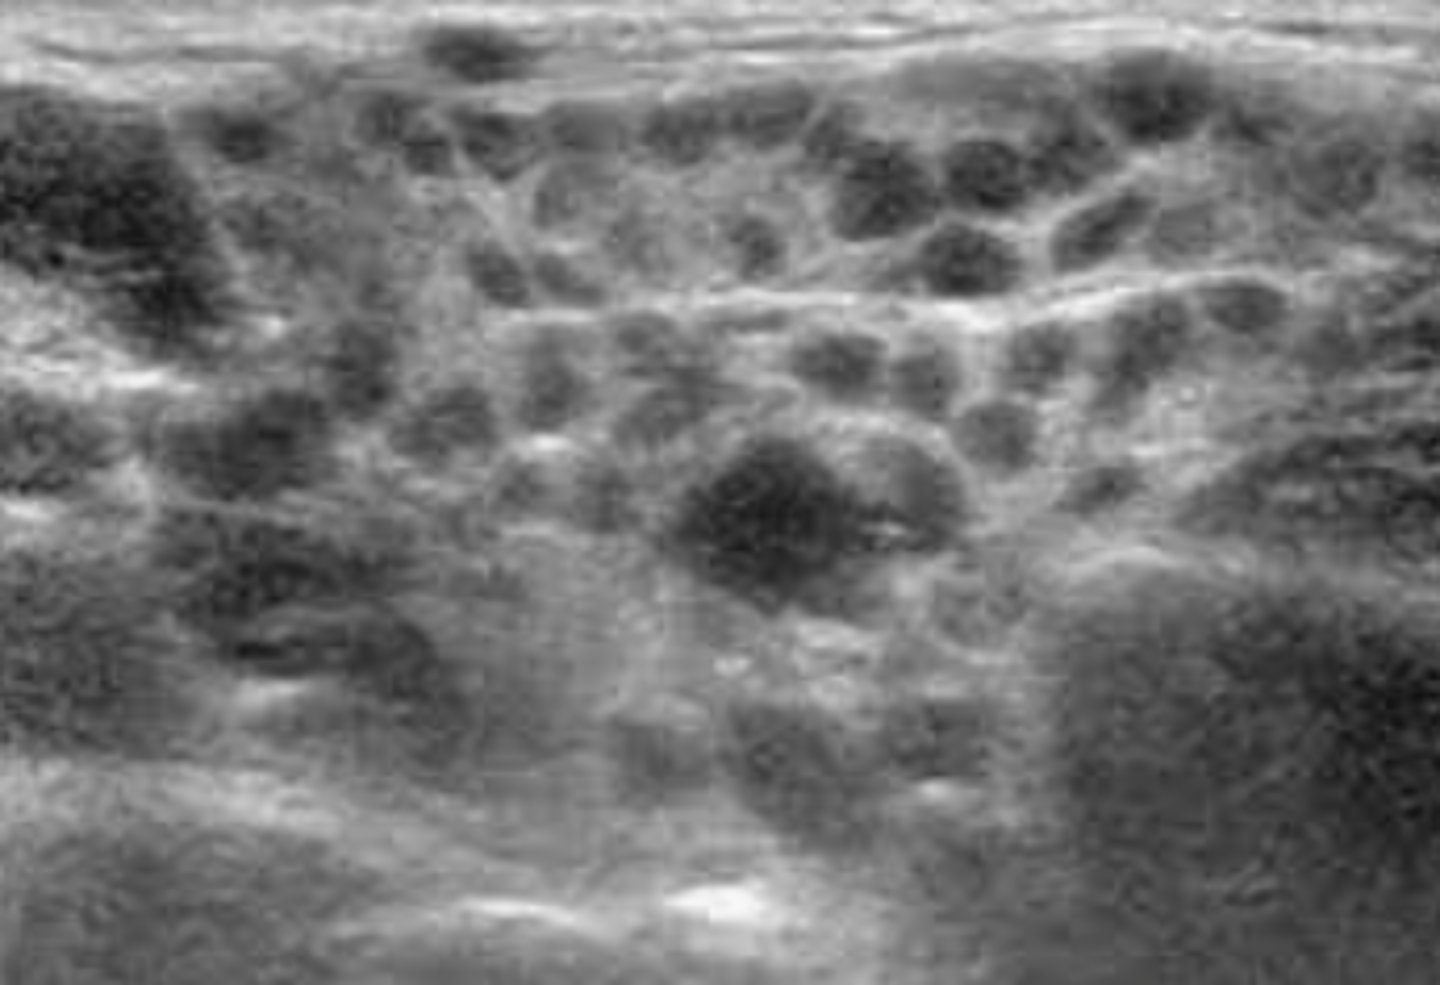

Benign Thyroid Neoplasms - Hashimoto disease:

Etiology

-Chronic ____ ____ disease

Clinical findings

-Often _____

-_____thyroidism

-Leukocytosis

-Sore _____

-_____

Sonographic findings

-_____ _____echoic thyroid glands

-_____vascular parenchyma

-Chronic lymphatic inflammatory disease

-Often painless

-Hypothyroidism

-Sore throat

-Fever

-Enlarged hypoechoic thyroid glands

-Hypervascular parenchyma